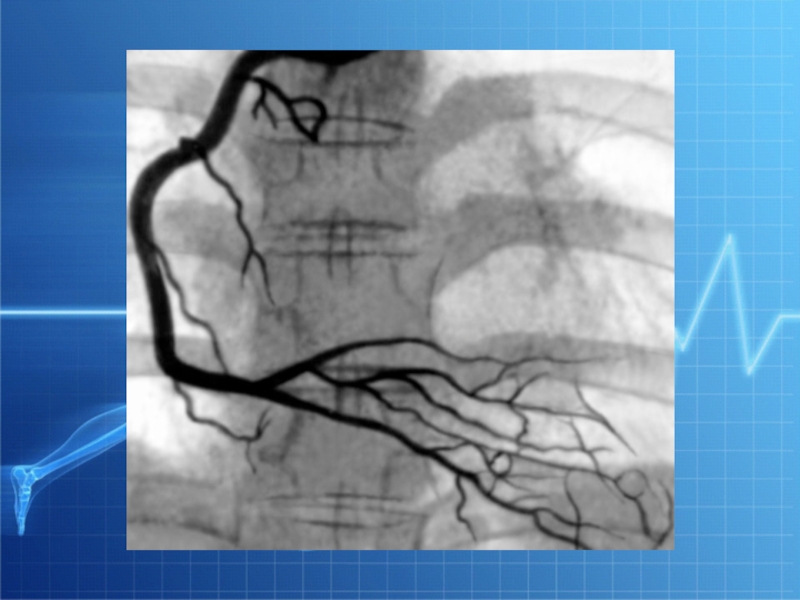

Слайд 18АНГИОГРАФИЯ (КОРОНАРОГРАФИЯ)

АНГИОГРАФИЯ (КОРОНАРОГРАФИЯ)